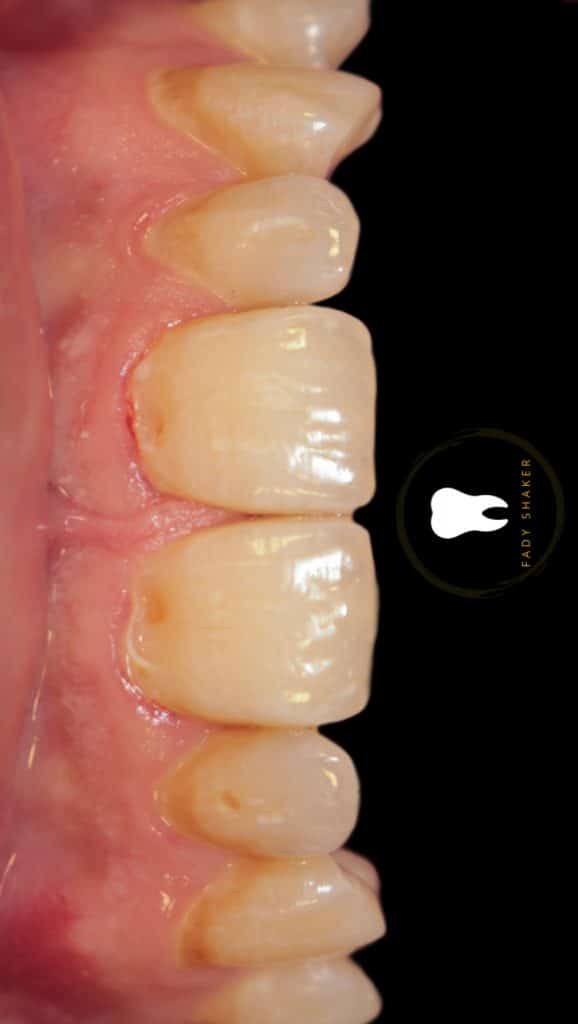

double class 5

not easy isolation game

1- teflon packing in the sulcus to retract gingival tissue&expose subginigval lesion

16- immediate result & waiting for rehydration